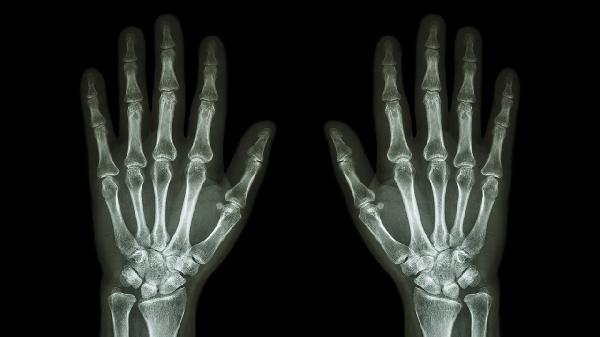

2、骨关节炎

该药膏适用于骨关节炎导致的关节软骨退变和骨质增生引发的不适。骨关节炎多见于中老年人,通常与关节劳损、肥胖、年龄增长等因素相关。症状表现为关节僵硬、摩擦感和间歇性疼痛。治疗中可能联合使用硫酸氨基葡萄糖胶囊保护软骨,或配合双氯芬酸二乙胺乳胶剂局部涂抹。